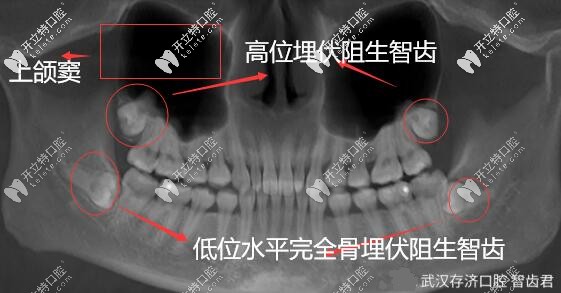

1.口腔檢查,需要拍攝X光片

2.各種錯(cuò)位牙、阻生牙和埋伏牙出現(xiàn)癥狀者。